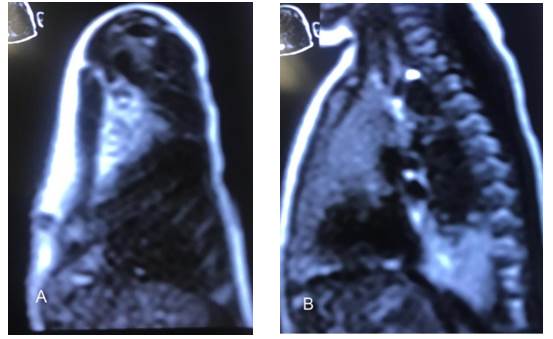

La figura 3 muestra las imágenes de la resonancia magnética nuclear en la recién nacida, en vista frontal y lateral. Se observa condensación basal derecha, en cuyo interior se observan múltiples imágenes serpiginosas, que sugieran ser quísticas de 1x1cm, resto de parénquima normal.

Figura 3. Resonancia magnética nuclear de neonato. A. Frontal. B. Lateral.